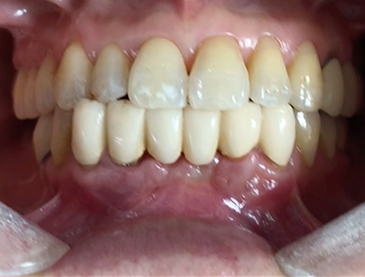

A clinical case using resorbable membrane

• A clinical case using resorbable membrane 2